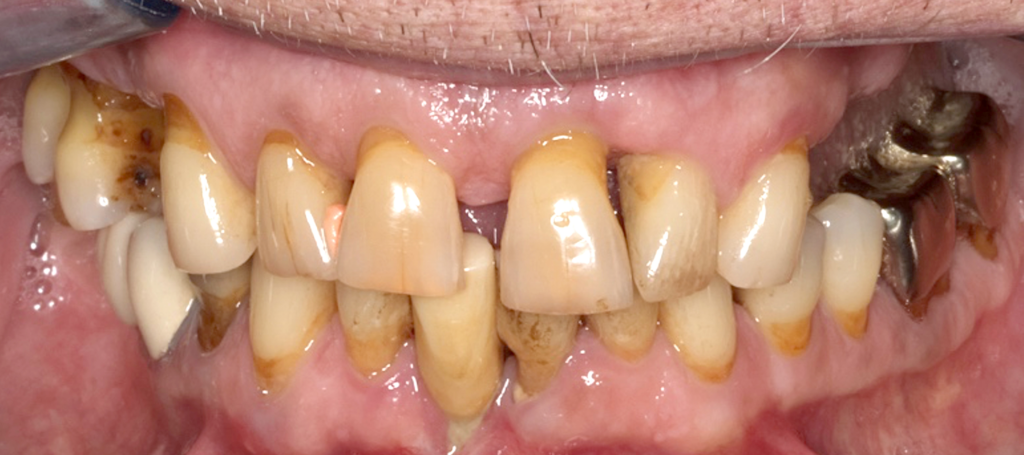

Pflegebedürftige Senior/-innenin der Praxis

Fragen Sie routinemäßig nach dem Pflegegrad bzw. nach einer Eingliederungshilfe: Rund 5,7 Millionen Patienten in Deutschland haben einen Pflegegrad und ca. 1 Millionen eine Eingliederungshilfe und sind damit anspruchsberechtigt für besondere zahnärztliche Leistungen nach § 22a SGB V.